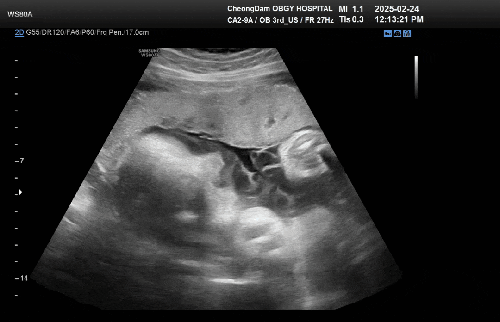

임신기록 : 시험관 임신 34주 2일차, 청담마리 막달 검사 그리고 제왕절개 수술 날짜를 잡다. #막달검사 #제대혈상담 #역아 #머리가큰아기 #탯줄이목에감기다 #제왕절개수술날짜

25년 2월 24일 월요일 시험관 임신 34주 2일차! * 이식일 : 24년 7월 17일 수요일 * 출산예정일 : 25년 4월...